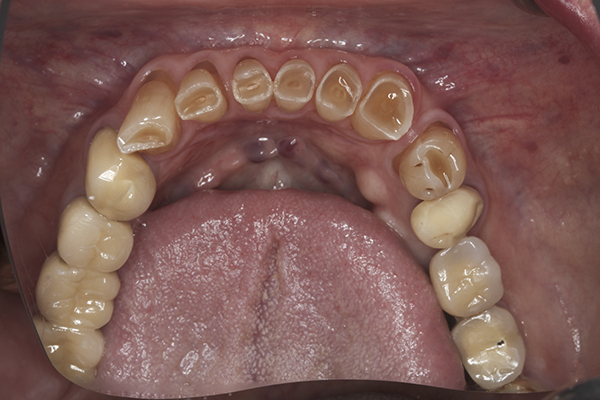

(42.) Postoperative mandibular occlusal view. Note the composite tops on teeth Nos. 28 through 31.

Figure 42